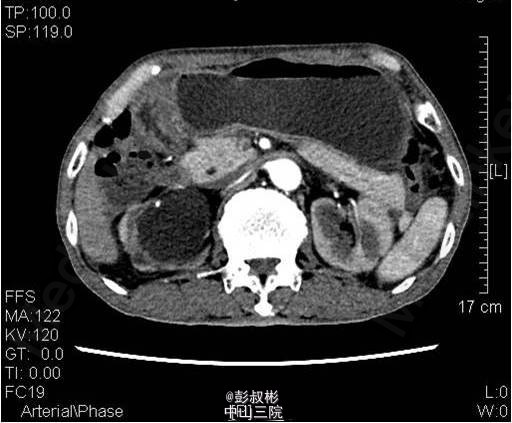

3、既往病史:既往“高血压”病史20年余,自服硝苯地平。“脑梗死”病史半年余,规律服用抗凝药物。 4、入院查体:无明显阳性体征。 实验室检查: 2015-01-11 肌酐101.2umol/L 。 2015-01-13总前列腺特异性抗原1.1ng/ml,游离前列腺特异性抗原0.3ng/ml。 2015-01-15 白细胞总数3.21x10E9/L,红细胞总数2.61x10E12/L,血红蛋白浓度78g/L,肌酐131umol/L ,白蛋白27g/L。 影像学检查: 2014-12-30心电图:完全性右束支传导阻滞。 2014-12-30全腹螺旋CT 检查所见:1、前列腺增生并钙化,建议MRI增强进一步检查除外合并肿瘤性病变。2、右侧盂管交界处结石并重度梗阻性肾积水,右肾结石;左肾多发钙化灶;左肾多发囊肿。3、慢性胆囊炎。4、双肺下叶多发小结节。 2015-01-14核素肾动态显像+GFR双血浆测定:右肾灌注、功能重度受损。左肾灌注正常,功能中度降低。肾小球滤过率:左肾为23.4ml/min,右肾为9.0ml/min。 2015-01-15彩超心脏:二尖瓣反流(轻度)。三尖瓣反流(轻度)。左室收缩功能正常。左室舒张功能减退。